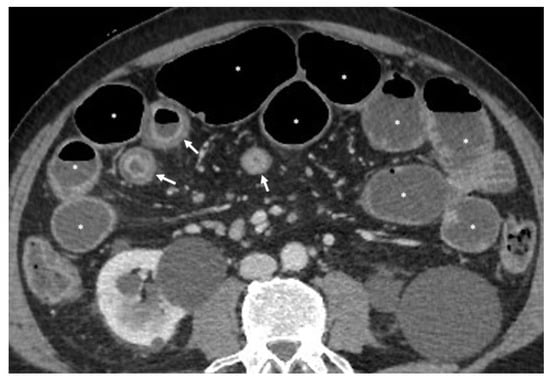

3. Is There a Small Bowel Stricture?

- The wall of a small bowel loop is defined thickened when its thickness (measured from mucosal to serosal layers) is more than 3 mm. According to the degree of thickness, small bowel thickening is defined as “mild” if the thickness is less than 1 cm, “moderate” if it is between 1 cm and 2 cm, and “marked” if it is more than 2 cm [20,21].

- Regarding the length of the bowel tract affected, a stricture is considered focal if it is less than 5 cm long, segmental if it is between 6 and 40 cm, and diffuse if it is longer than 40 cm [20,21,22]. In the case of multiple stenotic tracts, the healthy tracts interposed between the stenotic ones must not be considered.

- The minimum caliber of the lumen of the bowel loop affected by the stricture is typically considered pathological if it is less than 10 mm at the site of bowel wall thickening or if it is less than 50% compared to the adjacent bowel tracts [23]. Obviously, a correct valuation of this caliber presupposes good bowel preparation, in order to exclude false positives due to inadequate bowel loop distension.

- A normal bowel loop caliber ranges between 2 and 2.5 cm. A bowel lumen is dilated when it has a maximum diameter greater than 2.5–3 cm. The dilation is mild when the upstream lumen is dilated up to 4 cm and severe when it is more than 4 cm (Figure 3) [24]. Pre-stenotic bowel dilatation should always be checked, as it is a sign related to bowel obstruction. Moderate to severe stenosis was determined via double-contrast imaging (conventional barium study) with a sufficient amount of injected air, and stenosis was defined as stenosis in which the lumen was less than one half that of neighboring healthy intestine [25].